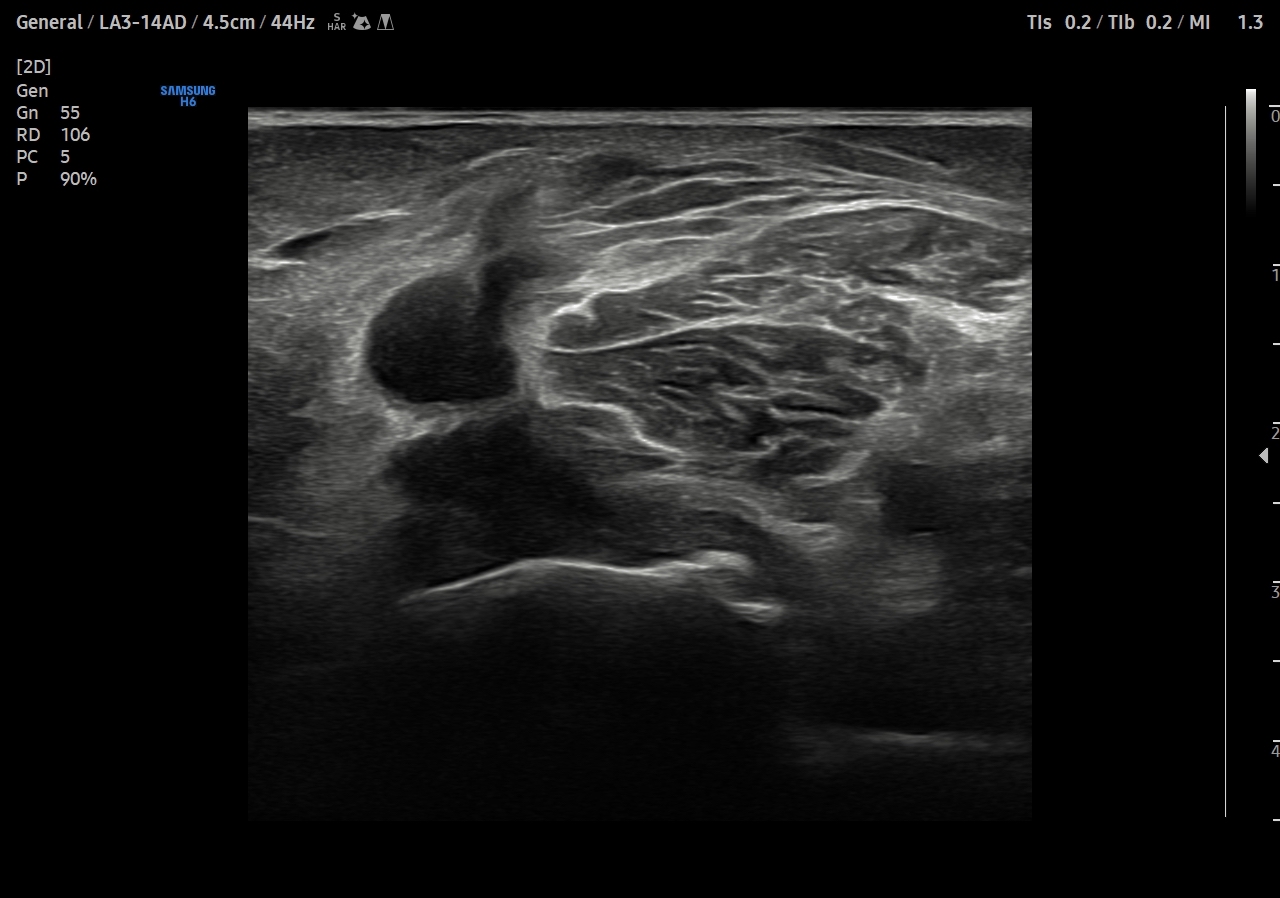

Descripción de los hallazgos ecográficos y las imágenes más relevantes para la resolución del caso

Se explora cara anterior, lateral y medial de rodilla sin hallazgos significativos. En cara posterior se explora el hueco poplíteo donde se visualiza en corte transversal una estructura hipoecoica con la base, el cuello entre el tendón del semimembranoso y el tendón de la cabeza medial del gemelo interno y el cuerpo. Sin signos de complicación. Permeabilidad del sistema venoso profundo.